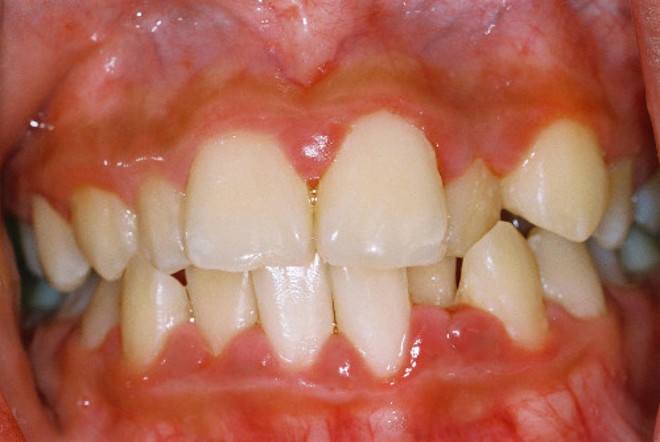

Гранулирующая форма болезни характеризуется существенным разрастанием десневой ткани, вследствие чего изменяется рельеф десны и наблюдается увеличение ее размеров. Изменяется и цвет десен, они приобретают ярко-красный оттенок. В результате отека и разрастания десневой ткани образуются ложные пародонтальные карманы, из которых может выделяться экссудат. При пальпации десны пациент отмечает болезненность ткани. Кровоточивость десен возникает при малейшем механическом, а изредка и при термическом, раздражении. Болезненность десен и их кровоточивость затрудняют прием пищи. Гранулирующая форма гипертрофического гингивита, как правило, является генерализованной, то есть поражение распространяется на десневую ткань, охватывающую большую группу зубов.

Гипертрофический гингивит принято классифицировать по трем степеням, каждая из которых определяется в соответствии со степенью разрастания десневой ткани.

Для первой степени характерно наличие валикообразного утолщения, которое наблюдается на протяжении всего зубного ряда и несколько выступает в преддверие рта.

Вторая степень заболевания характеризуется наплыванием десневого края на коронки зуба, при этом коронка зуба может покрываться десневой тканью вплоть до ½ от своей высоты. Межзубные сосочки существенно увеличены, десневой край приподнят, а валикообразное утолщение тянется вдоль всего зубного ряда.